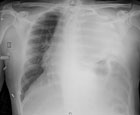

Cancer du poumon

Cas a discuter

Source : e-Thorax février 2015

Il s'agit d'un dosage des marqueurs de tumeur germinale.

Le taux d'alphafoetoprotéine était de 3 300 ng/m/l ; d'où le titre du cas clinique.

Le taux de béta HCG est de 80 U/l.

Il s'agit donc d'une tumeur